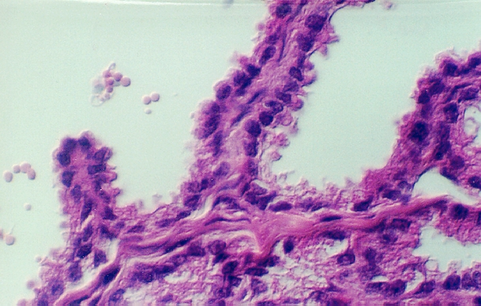

The lumen of this gland is thrown into many folds that appear to branch. This creates a labyrinth of channels, tubes, and pockets into which the secretory product flows. The epithelium shown in the photos below may be simple columnar with patches of pseudostratified epithelium. The appearance of the epithelium is variable and dependent on age and the level of androgen production. One can see some lipochrome pigment in the epithelium, which is present in elderly males. Look at the wall of the gland and again, there are numerous bundles of smooth muscle.

What does the seminal vesicle contribute to the semen?